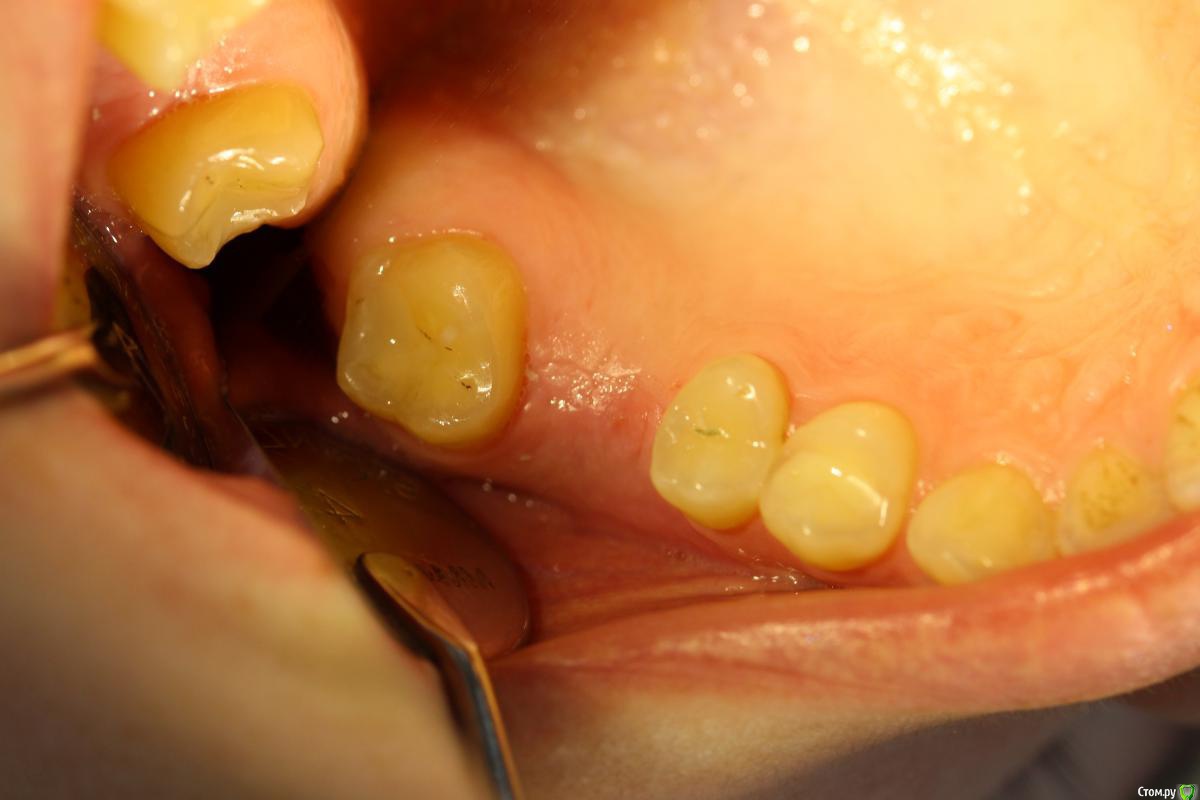

Norton Опубликовано 14 апреля, 2019 Поделиться Опубликовано 14 апреля, 2019 (изменено) Доброго времени суток уважаемые коллеги. Ко мне обратилась пациентка с установленным импл. в области верхней 6 (XIVE 3.8 / 11 мм). Сейчас назревает вопрос нужна ли мягкотканная пластика или нет? Cмутило то, что несколько коллег в моем городе порекомендовали сделать. Изменено 14 апреля, 2019 пользователем Norton Ссылка на комментарий

Norton Опубликовано 17 апреля, 2019 Автор Поделиться Опубликовано 17 апреля, 2019 (изменено) Покажите фото внутриротовоеФото Изменено 17 апреля, 2019 пользователем Norton Ссылка на комментарий

Дмитрий М Опубликовано 18 апреля, 2019 Поделиться Опубликовано 18 апреля, 2019 (изменено) отлом вестибулярной или миграция графта?похоже свободный фрагмент, пальпируется нет? Изменено 18 апреля, 2019 пользователем Дмитрий М Ссылка на комментарий

Magadalina Опубликовано 19 апреля, 2019 Поделиться Опубликовано 19 апреля, 2019 Похоже на выход графта сразу после синус- лифтинга через окно. Это никакого значения не имеет Ссылка на комментарий